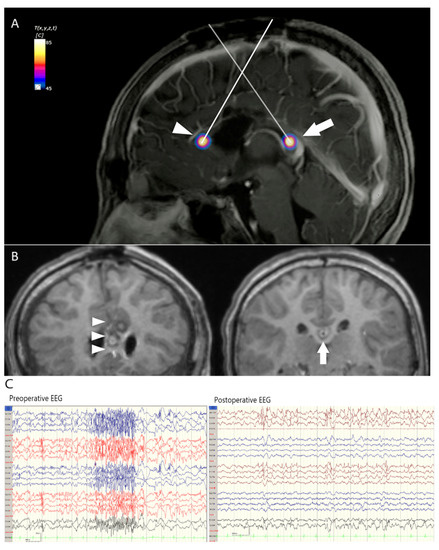

3.4. Case 3. Intractable Seizure Secondary to Arteriovenous Malformation (AVM,)

| 3 | Female | 45 | Left mesial temporal AVM | Stereotactic radiosurgery | Left mesial temporal (around residual vein) | 2 | 3941.89 | 4073 (3.2%) | 1 | 3 | none | 1a |